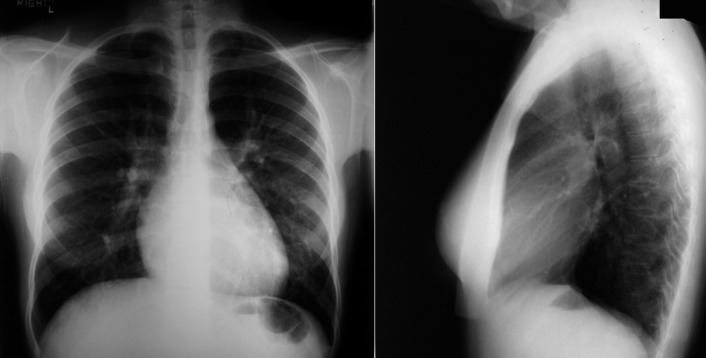

A patent foramen ovale is present in 25% to 30% of the adult population ( Figs. 18-1 to 18-4 ). Any magnitude of shunting across it in normal circumstances is undetectable radiographically. Percutaneous patent foramen ovale closure devices are fairly commonly inserted and are radiographically evident.

See Figures 18-5 to 18-31 . Possible findings are discussed in the following sections.